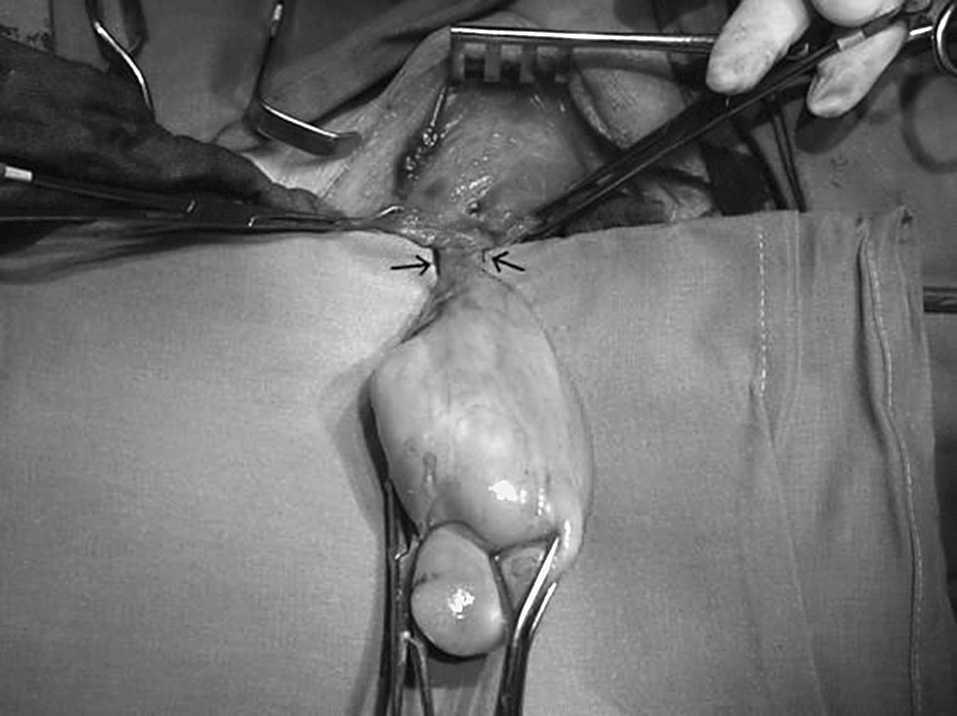

Paciente de 73 años, con antecedentes de exéresis de pólipos faríngeos hace 8 y 18 años y exéresis de lipoma de seno piriforme hace 6 meses, que es remitido por el otorrinolaringólogo por persistencia de clínica de disfagia alta tras la cirugía, sin otros síntomas. Se le practica una endoscopia digestiva, que informa de tumor submucoso de 8 cm en el tercio superior de esófago, que afecta desde boca de Killian hasta tercio medio esofágico. Con la sonda de ecoendoscopia se visualiza una masa ecogénica de 1,5 cm de diámetro que procede de submucosa e indica lipoma esofágico. En el tránsito baritado se aprecia un defecto de repleción de unos 10 cm de longitud que ocupa la totalidad de la luz esofágica (fig. 1). En la resonancia magnética se visualiza una tumoración del mediastino posterior hiperintensa en las imágenes potenciadas en T1 y T2, cuyo polo superior depende de esófago cervical. La tomografía computarizada cervicotorácica informa de una tumoración cervical intraesofágica de 10 × 3,5 × 4 cm, de características radiológicas compatibles con tejido graso. Ante estos hallazgos se decidió intervención quirúrgica. Mediante un abordaje por cervicotomía lateral izquierda, se procedió a la disección del esófago cervical y esofagotomía longitudinal; se visualizó una masa elástica que ocupaba la totalidad de la luz esofágica y se procedió a su extracción. La tumoración medía unos 10 cm, con una base de implantación fina en la pared posterior del esófago cervical (fig. 2). Se procedió a resección y posterior esofagorrafia. El postoperatorio fue satisfactorio, y se dio el alta al sexto día.

Fig. 2. Cirugía: lipoma exteriorizado por cervicotomía con base de implantación.